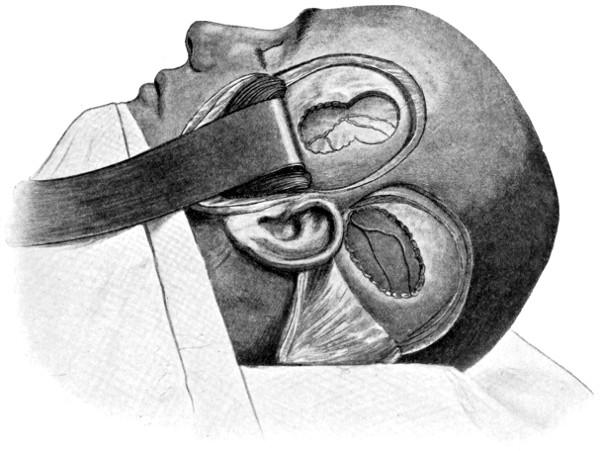

| 45-48. Intermusculo-temporal cerebral decompression | 122, 123 |

| 52 A and B. The operative treatment of middle meningeal hæmorrhage | 144, 145 |